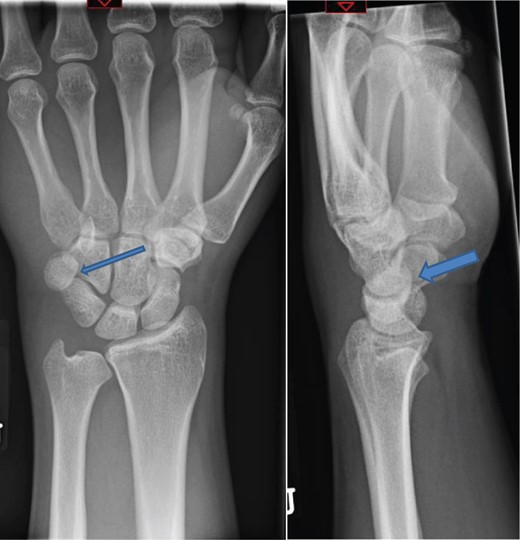

The X-rays of the patient was later reviewed by the duty radiologist and reported as a suspected dislocation of the pisiform bone, Fig. 1. Therefore the patient was recalled to the trauma clinic after three days. He was reassessed and a further three dimensional scan of the wrist was arranged. The CT scan demonstrated distal dislocation of the pisiform which appeared to lie in a ‘locked’ position beyond the distal triquetrum, Fig. 2.

CT showing pisiform displaced from its anatomical position confirming dislocation.